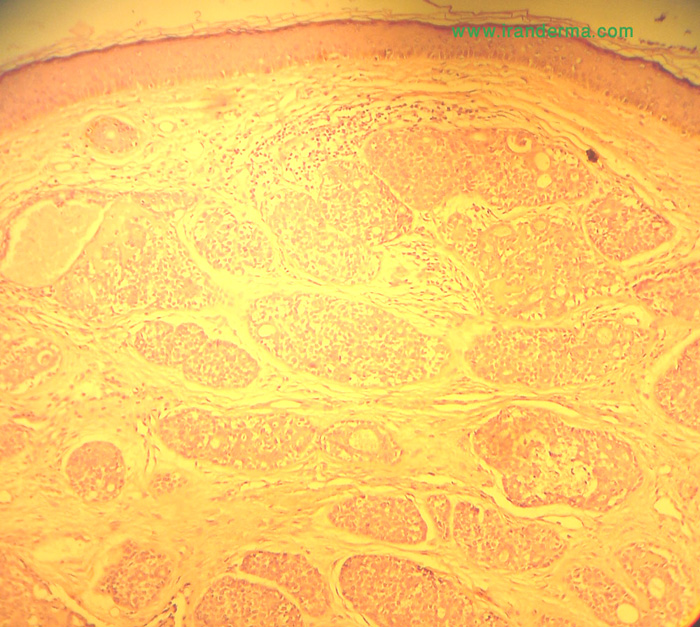

What is your diagnosis for this 60-year-old man?

He had this solitary asymptomatic nodule on his nose since several months earlier. No any other significant findings....

Diagnosis: Cylindroma

Cylindroma is a benign tumour in which apocrine and trichoepitheliomatous differentiation has been noted indicating complex hair follicle (folliculo-sebaceous-apocrine) rather than eccrine differentiation.

Histologically cylindroma is a circumscribed, non-encapsulated , dermal tumour without attachment to the epidermis . The lesion is composed of numerous oval and polygonal nests arranged in an interlocking 'jigsaw-like' pattern. There are two cell types, the peripheral cells are small and basophilic and central cells are larger and pale stained. Small ductal lumina may be present. Thick PAS positive hyaline bands surround tumour islands. Hyaline droplets within nests.